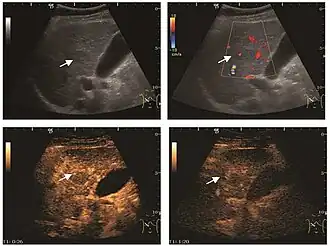

Hepatic hemangioma (2D). The lesion is located in the left hepatic lobe. Note precise delineation, their increased echogenity and the heterogeneous internal structure.

Hepatic hemangioma (CEUS). Progression of CA from the periphery toward the center of the lesion is evidenced by examination at various time intervals (a – arterial phase; b – late phase).

It is the most common liver tumor with a prevalence of 0.4 – 7.4%. It is generally asymptomatic but also can be associated with pain complaints or cytopenia and/or anemia when it is very bulky. It is unique or paucilocular. It can be associated with other types of benign liver tumors. Characteristic 2D ultrasound appearance is that of a very well defined lesion, with sizes of 2–3 cm or less, showing increased echogenity and, when located in contact with the diaphragm, a "mirror image" phenomenon can be seen. When palpating the liver with the transducer the hemangioma is compressible sending reverberations backwards. Doppler exploration reveals no circulatory signal due to very slow flow speed. CEUS investigation has real diagnosis value due to the typical behavior of progressive CA enhancement of the tumor from the periphery towards the center. The enhancement is slow, during several minutes, depending on the size of hemangioma and on the presence (or absence) of internal thrombosis. During late (sinusoidal) phase, if totally "filled" with CA, hemangioma appears isoechoic to the liver. Deviations from the above described behavior can occur in arterialized hemangiomas or those containing arterio-venous shunts. In these cases, differentiation from a malignant tumor is difficult and requires other imaging procedures, follow up and measurements of the tumor at short time intervals.[4]